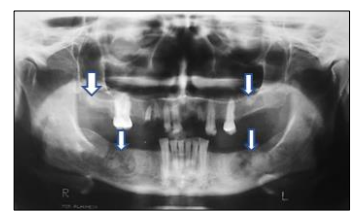

Paciente, 48 anos, sexo feminino, melanoderma, apresentou-se para consulta odontológica com radiografia panorâmica, solicitada por um cirurgião-dentista para programação cirúrgica de raízes residuais. Ao analisar a radiografia, foram observadas áreas radiopacas permeadas por áreas radiolúcidas nas regiões posteriores da mandíbula (quadrante posterior direito e esquerdo). Na maxila, foram identificadas duas áreas radiopacas localizadas nos quadrantes posteriores de ambos os lados (direito e esquerdo). As lesões eram assintomáticas e não provocavam nenhuma alteração nas corticais; portanto, se tratava de achado radiográfico. Nenhuma outra informação da saúde da paciente foi digna de nota. Analise a radiografia a seguir:

Após análise dos aspectos clínicos e radiográficos, assinale a conduta correta a ser instituída para a paciente em relação às lesões observadas.